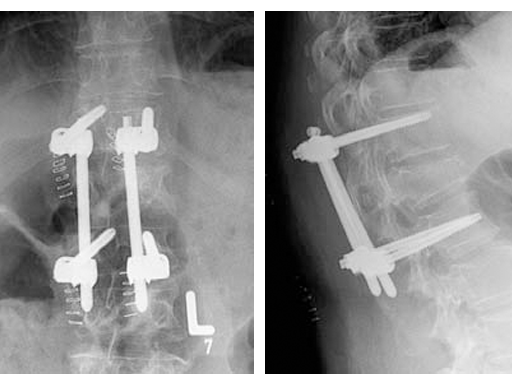

Based on the preoperative analysis and the surgical plan, the patient was positioned supine for the first surgery and the fracture was stabilized with a bridging construct (T12-L2) from posterior. Due to the ruptured disc, an anterior reconstruction of the spine was planned for a later stage surgery. The posterior stabilization was considered to be sufficient to bridge the fracture and time between both surgeries.

Using the USS Fracture MIS system for the initial stabilization allowed for a minimally invasive approach with intraoperative active reduction of the spinal fracture. The unique design of the fracture clamp allowed for independent correction of the sagittal alignment (Fig a) as well as height readjustment (Fig b).

For this patient, independent lordosis correction, height readjustment, and spinal stabilization were the primary goal of surgery. As percutaneous toploading pedicle screw systems cannot provide independent correction of the flexion-compression deformity, the fracture clamps and Schanz screws of the USS Fracture MIS system were used to overcome this disadvantage.

Due to the minimally invasive approach, the patient experienced less blood loss and muscle trauma compared to the traditional open approach.